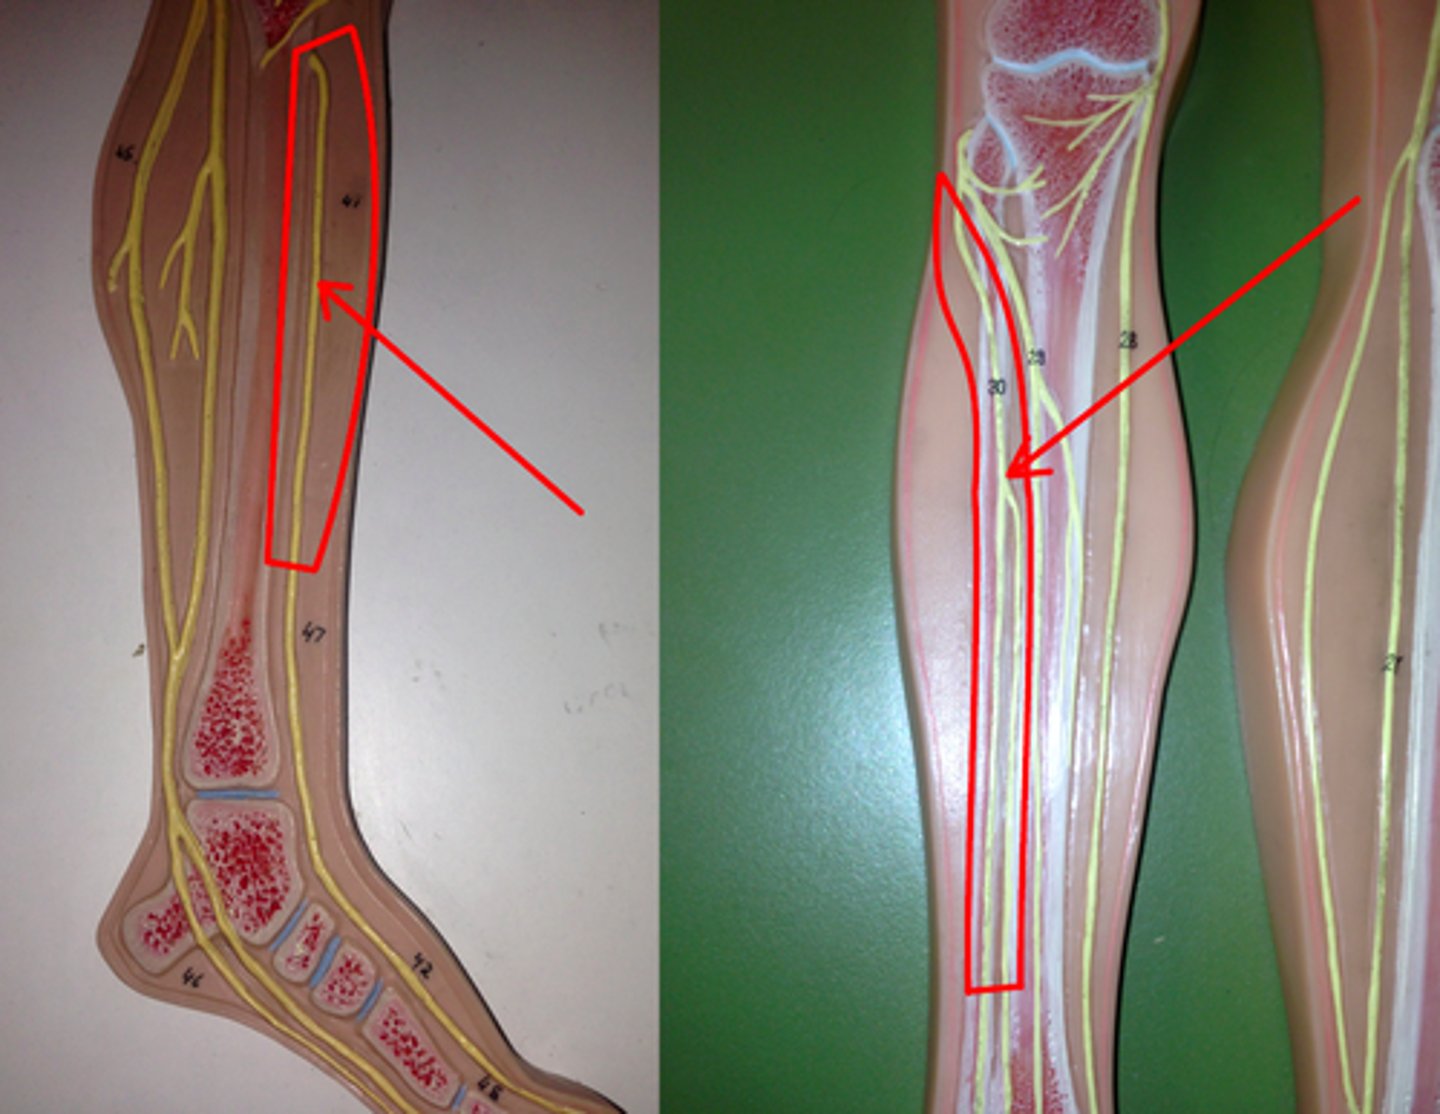

sciatic nerve

tibial nerve

common fibular nerve

obturator nerve